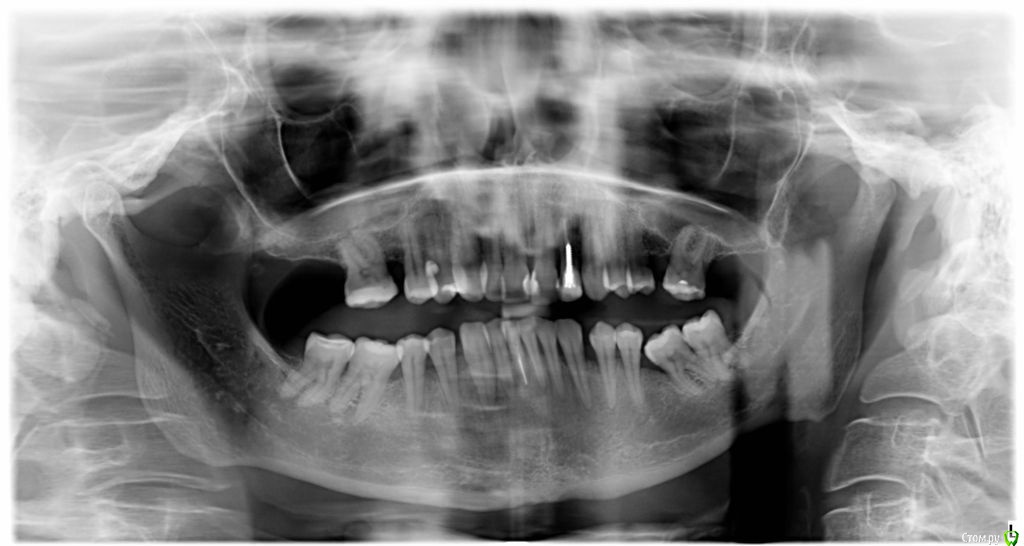

VVQW Опубликовано 25 октября, 2016 Поделиться Опубликовано 25 октября, 2016 (изменено) добрый день. Сложная ситуация. Более 10 лет назад ставили брекеты без анализов, диагностик, снимков и пр. Сейчас, что имееем, то и имеем. Большую проблему. Прикуса нет. Клиновидки из-за перегруза. Что можно сделать прошу совета и помощи. Обращалась за консультацией ко многим специалистам, мнения разнятся от слегка положительного, до просто критической ситуации. Последний профессор ортодонт вообще сказал - все вырвать и поставить протезы. УЖАС..... Может кто-нибудь из врачей даст совет... очень на Вас надеюсь. С уважением. Изменено 25 октября, 2016 пользователем VVQW Ссылка на комментарий

VVQW Опубликовано 6 декабря, 2016 Автор Поделиться Опубликовано 6 декабря, 2016 (изменено) Лечение скорее всего будет неким компромисом. Я правильно понимаю, 10 лет назад сняли брекеты?Брекеты были сняты более 10 лет назад. Ретейнеры не ставились. Верхние 6-ки по решению врача были убраны для задвигания зубов к заду, верхние 8-ки - не выросли. Нижние 6-ки - удалены в подростковом возрасте, до 14 лет. http://s019.radikal.ru/i641/1612/eb/3498e6cec3f8.jpg http://s018.radikal.ru/i518/1612/73/739600b6d2d1.jpg http://s011.radikal.ru/i318/1612/73/443e1513aaf8.jpg http://s017.radikal.ru/i403/1612/86/73e0dfe4ca62.jpg http://s018.radikal.ru/i518/1612/a2/bd7078537d9e.jpg http://s017.radikal.ru/i417/1612/9d/41b6d1c98666.jpg http://s019.radikal.ru/i642/1612/fe/3222fa19d517.jpg Гипсовых моделей нет, зубы неподвижны. http://s019.radikal.ru/i639/1612/56/1345f17db908.jpg http://s019.radikal.ru/i630/1612/55/145ef7c813b2.jpg http://s017.radikal.ru/i440/1612/c2/74bd4da2643e.jpg http://s008.radikal.ru/i303/1612/b4/e80683ed7d2b.jpg http://s010.radikal.ru/i314/1612/74/6d2f9671b0d5.jpg http://s018.radikal.ru/i502/1612/97/9a15fcf4ddd3.jpg http://s020.radikal.ru/i715/1612/59/9bb4a006621f.jpg Изменено 6 декабря, 2016 пользователем VVQW Ссылка на комментарий

VVQW Опубликовано 6 декабря, 2016 Автор Поделиться Опубликовано 6 декабря, 2016 Брекеты были сняты более 10 лет назад. Ретейнеры не ставились. Верхние 6-ки по решению врача были убраны для задвигания зубов к заду, верхние 8-ки - не выросли. Нижние 6-ки - удалены в подростковом возрасте, до 14 лет.зубы неподвижны. Ссылка на комментарий

Brigita Опубликовано 6 декабря, 2016 Поделиться Опубликовано 6 декабря, 2016 (изменено) У Вас сложный случай, но лечение было бы возможным, если бы не резорбция корней верхней челюсти. Ортодонт принимая решение о лечении такого пациента должен понимать, что он берет на себя большую юридическую ответственность. Я думаю, все это Вам уже говорили. Ищите опытного врача и будьте готовы к вложению средств и потерям зубов... Скорее всего имплантация неизбежна и фронтального и частично бокового отдела.Сколько Вам лет? Изменено 6 декабря, 2016 пользователем Brigita Ссылка на комментарий